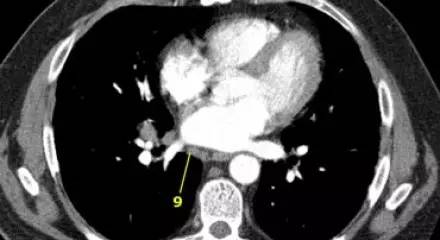

肺 CT 横断面上的肺韧带淋巴结(9)